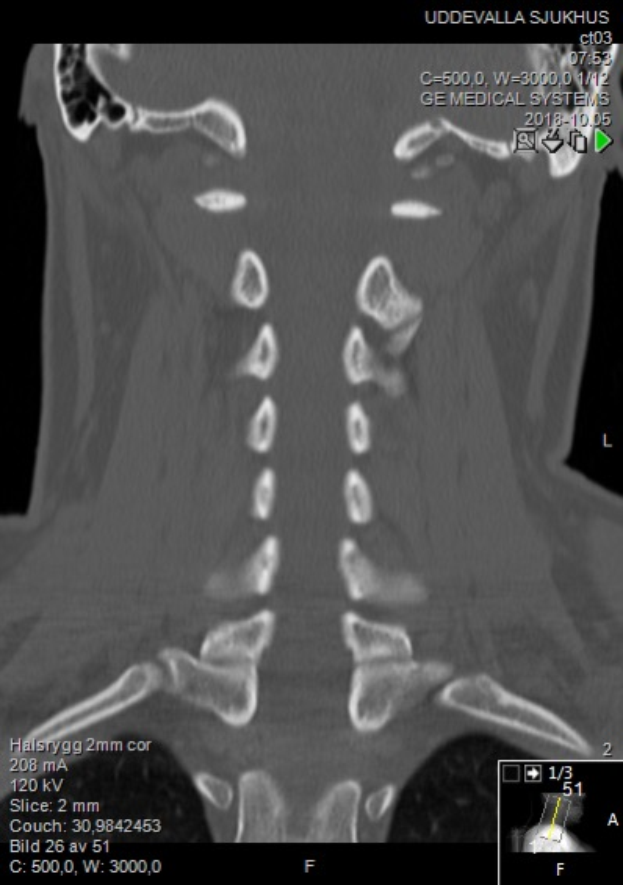

Eine MRT-Aufnahme des Halses eines Mannes mit einer sichtbaren Fraktur, die auf einem Computerbildschirm angezeigt wird.Laurenz Mühle